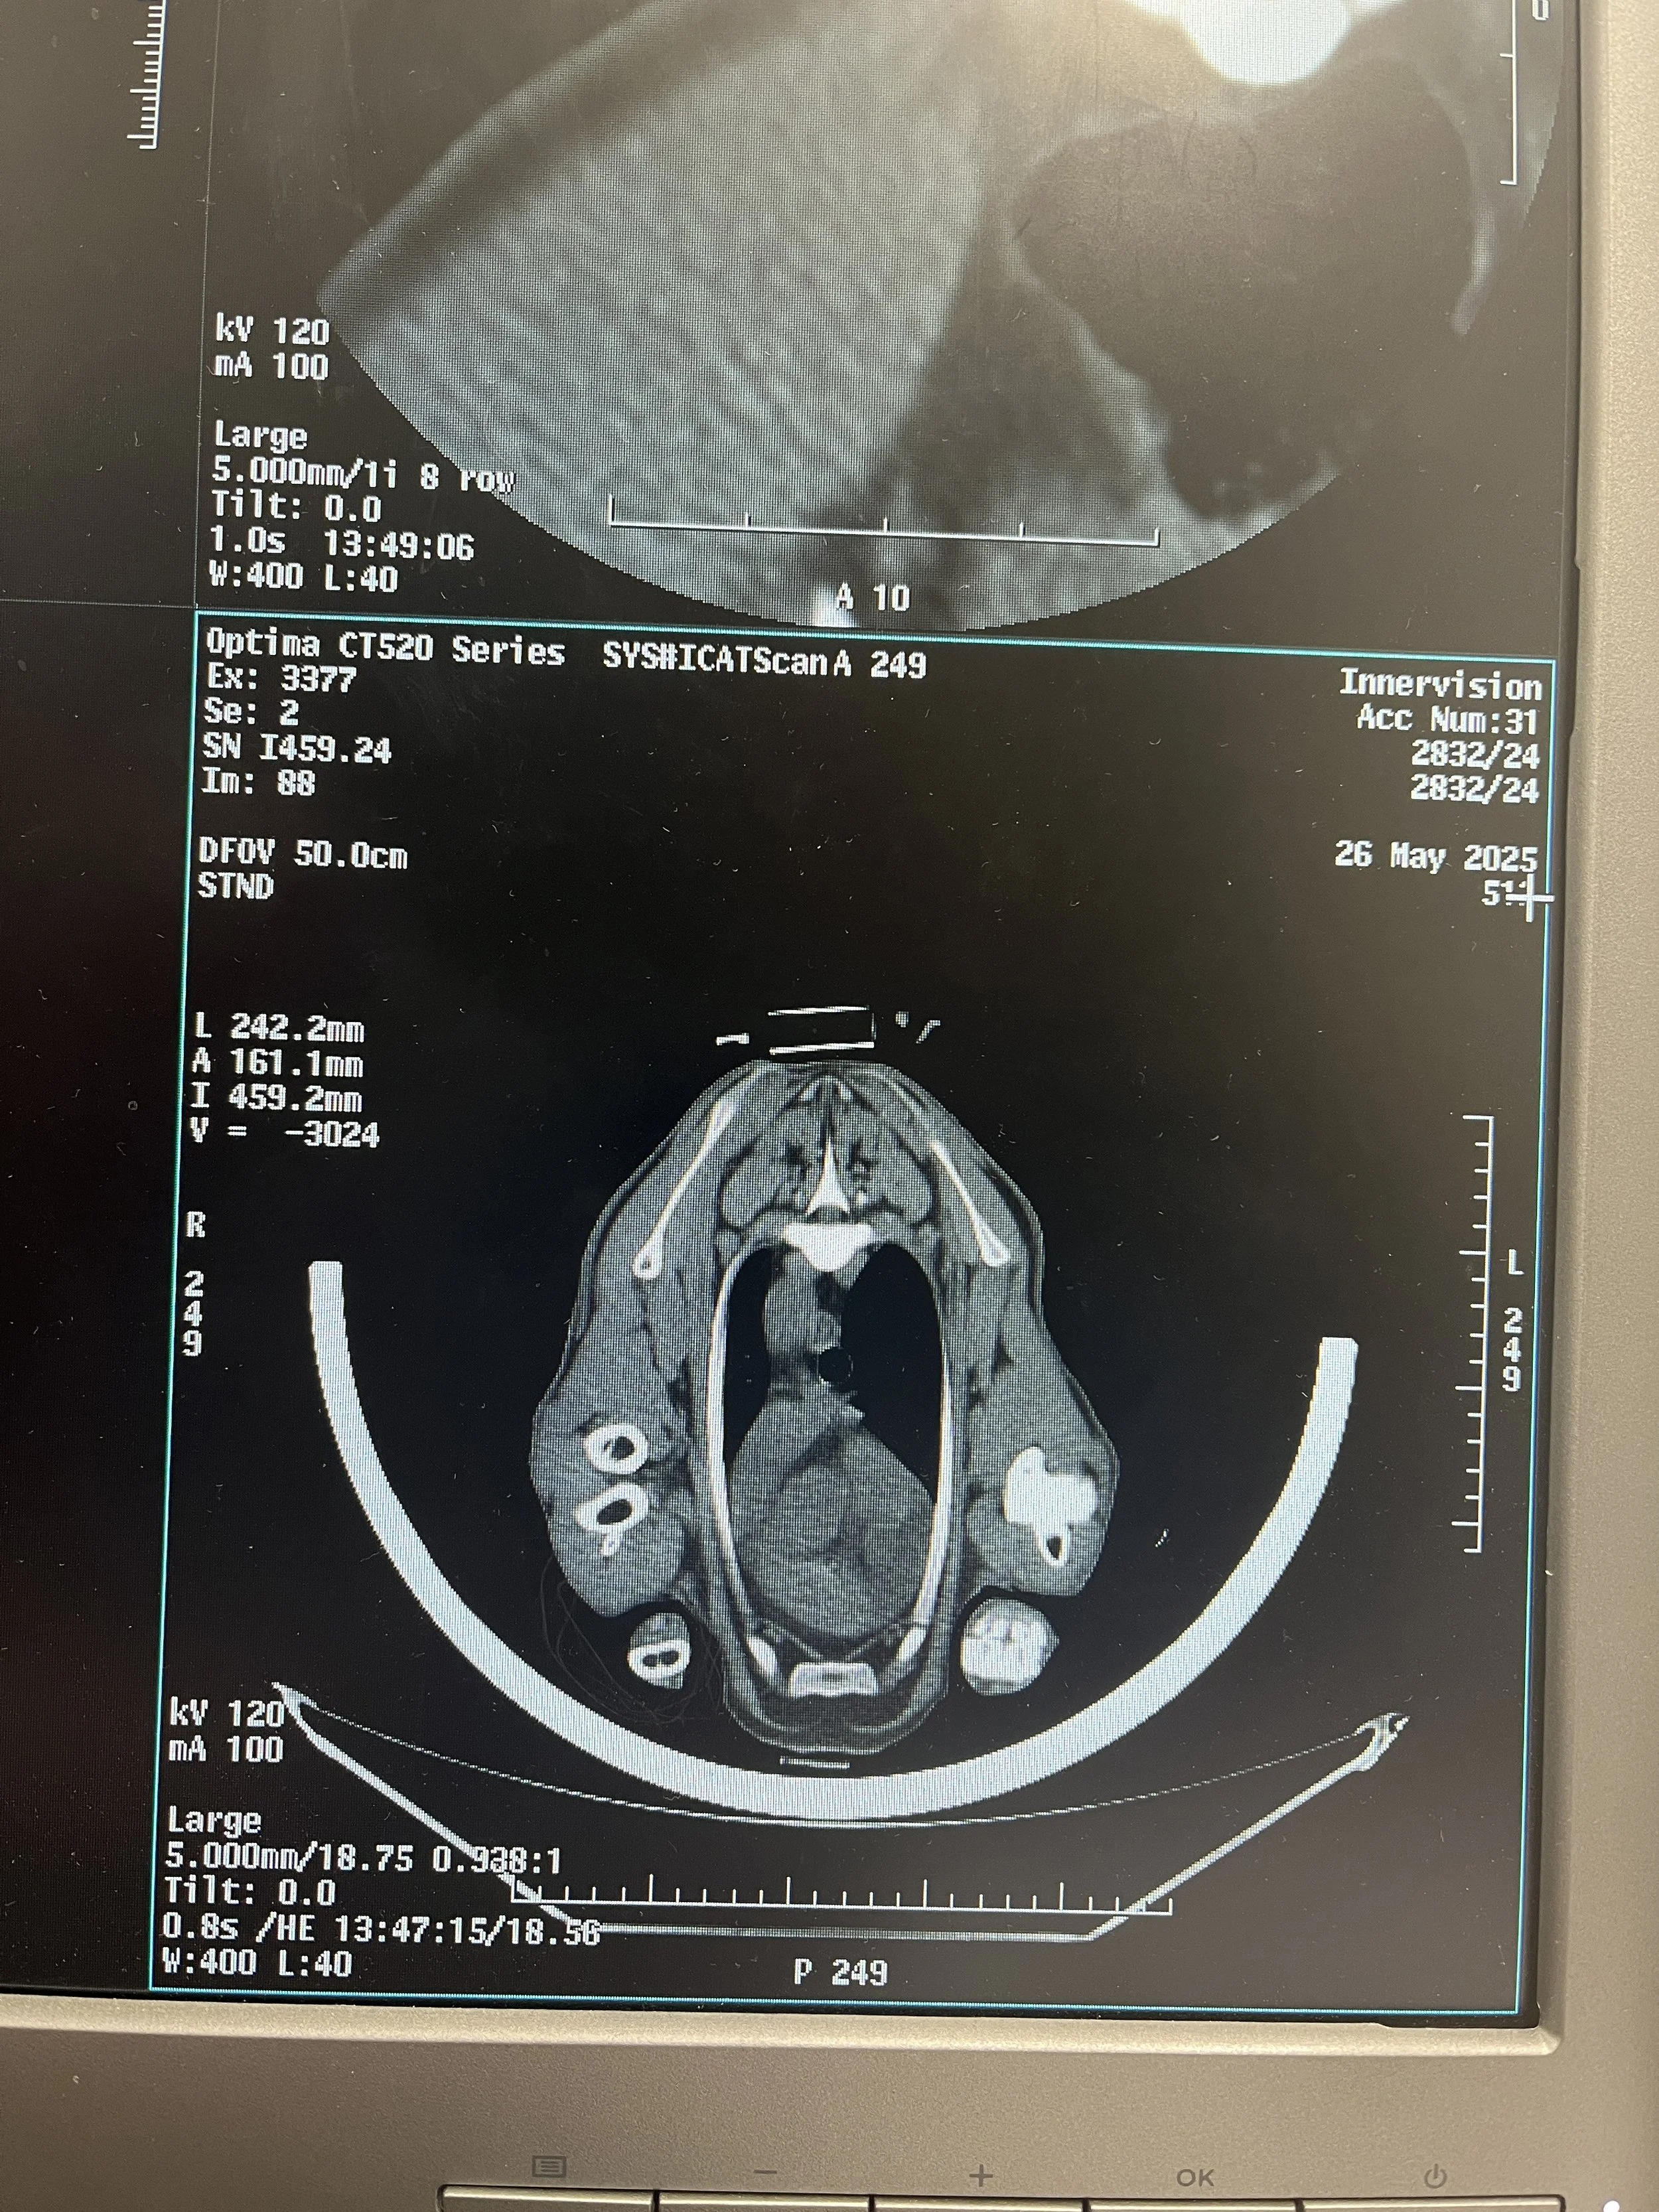

Cross-sectional images through a body, to accurately measure the weight, volume and density of muscle, fat and bone in a live animal, removing the need to slaughter the animal and dissect the carcass.

CT scanners use x-rays to produce cross-sectional images through a body. This technology allows the evaluation of high value breeding animals in meat production, looking at the weight of muscle and fat in the hindleg, loin and shoulder primal cuts which are closely related to the newer grading systems. It has been found that when used in conjunction with ultrasound scanning, it can almost double the rate of genetic progress.

More recently the use of AI algorithms and spiral CT scans have improved the ability to look at whole body composition which means we can now start to look deeper into specific organs such as the rumen or lungs; rumen in relation to methane emission and feed intake and lungs providing the ability to detect lung lesions that may indicate pneumonia.